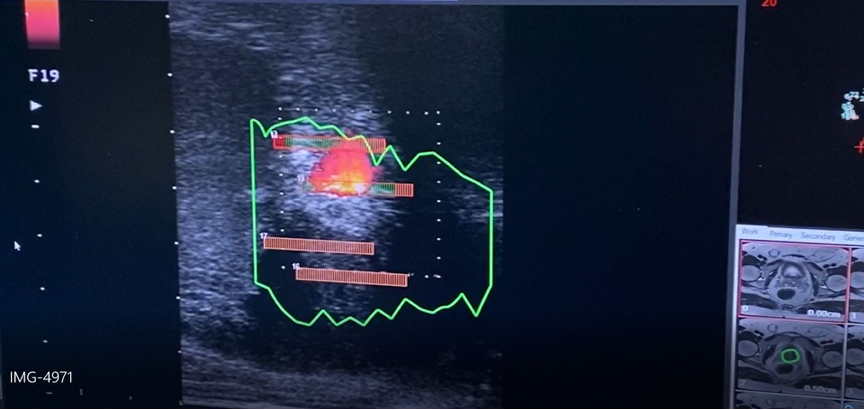

«Σε σχέση με άλλους τύπους λέιζερ απορροφάται καλύτερα από τον προστατικό ιστό και πολύ γρήγορα, μειώνοντας σημαντικά το χρόνο επέμβασης αλλά επιτρέπει και την διαδερμική με βελόνα εφαρμογή στην περιοχή του περινέου (δηλ. μεταξύ των όρχεων και του πρωκτού) χωρίς να χρειάζεται να εισέλθει δια μέσω της ουρήθρας. Αυτό σημαίνει ότι κάλλιστα μπορεί να εφαρμοσθεί μόνο με τοπική αναισθησία», επισημαίνει ο κ. Νικόλαος Μερτζιώτης, Χειρουργός, Ουρολόγος – Ανδρολόγος, Διδάκτωρ Πανεπιστημίου Αθηνών, Μετεκπαιδευθείς στο UCL της Μεγάλης Βρετανίας, Διευθυντής Ουρολογικής Κλινικής, Επανορθωτικής και Χειρουργικής Ανδρολογίας του Metropolitan General.

Η συχνουρία, η δυσκολία στην ούρηση, η διακοπτόμενη ούρηση, το αίσθημα ότι δεν έχει αδειάσει εντελώς η κύστη και η ανάγκη να τρέξουμε στην τουαλέτα, είναι μερικά από τα συμπτώματα που είναι κοινά στις δύο κύριες παθήσεις του προστάτη, δηλαδή την καλοήθη υπερπλασία και τον κακοήθη όγκο του προστάτη. Αυτά τα συμπτώματα αφορούν άνδρες κατά κύριο λόγο από την ηλικία των 45 ετών και άνω. Με την ίνα του λέιζερ καταστρέφεται ο υπερπλαστικός ιστός του προστάτη, ενώ τις επόμενες ημέρες συνεχίζεται η καταστροφή δια μέσω της φυσιολογικής διαδικασίας που ονομάζεται πηκτική νέκρωση έτσι ώστε ακόμα μεγαλύτερη ποσότητα προστατικού ιστού να νεκρώνεται, επιτρέποντας την καλύτερη ούρηση. Με τη μέθοδο αυτή οι άνδρες καταφέρνουν να διατηρήσουν την εκσπερμάτισή τους σε ποσοστά μεγαλύτερα του 90% και μπορούν να τεκνοποιήσουν. Οπότε, απευθύνεται κυρίως σε νεότερους άνδρες που ακόμα δεν έχουν τεκνοποιήσει χωρίς βέβαια να αποκλείονται οι μεγαλύτερες ηλικίες.

Η εστιακή θεραπεία με φωτοεξάχνωση (laser)